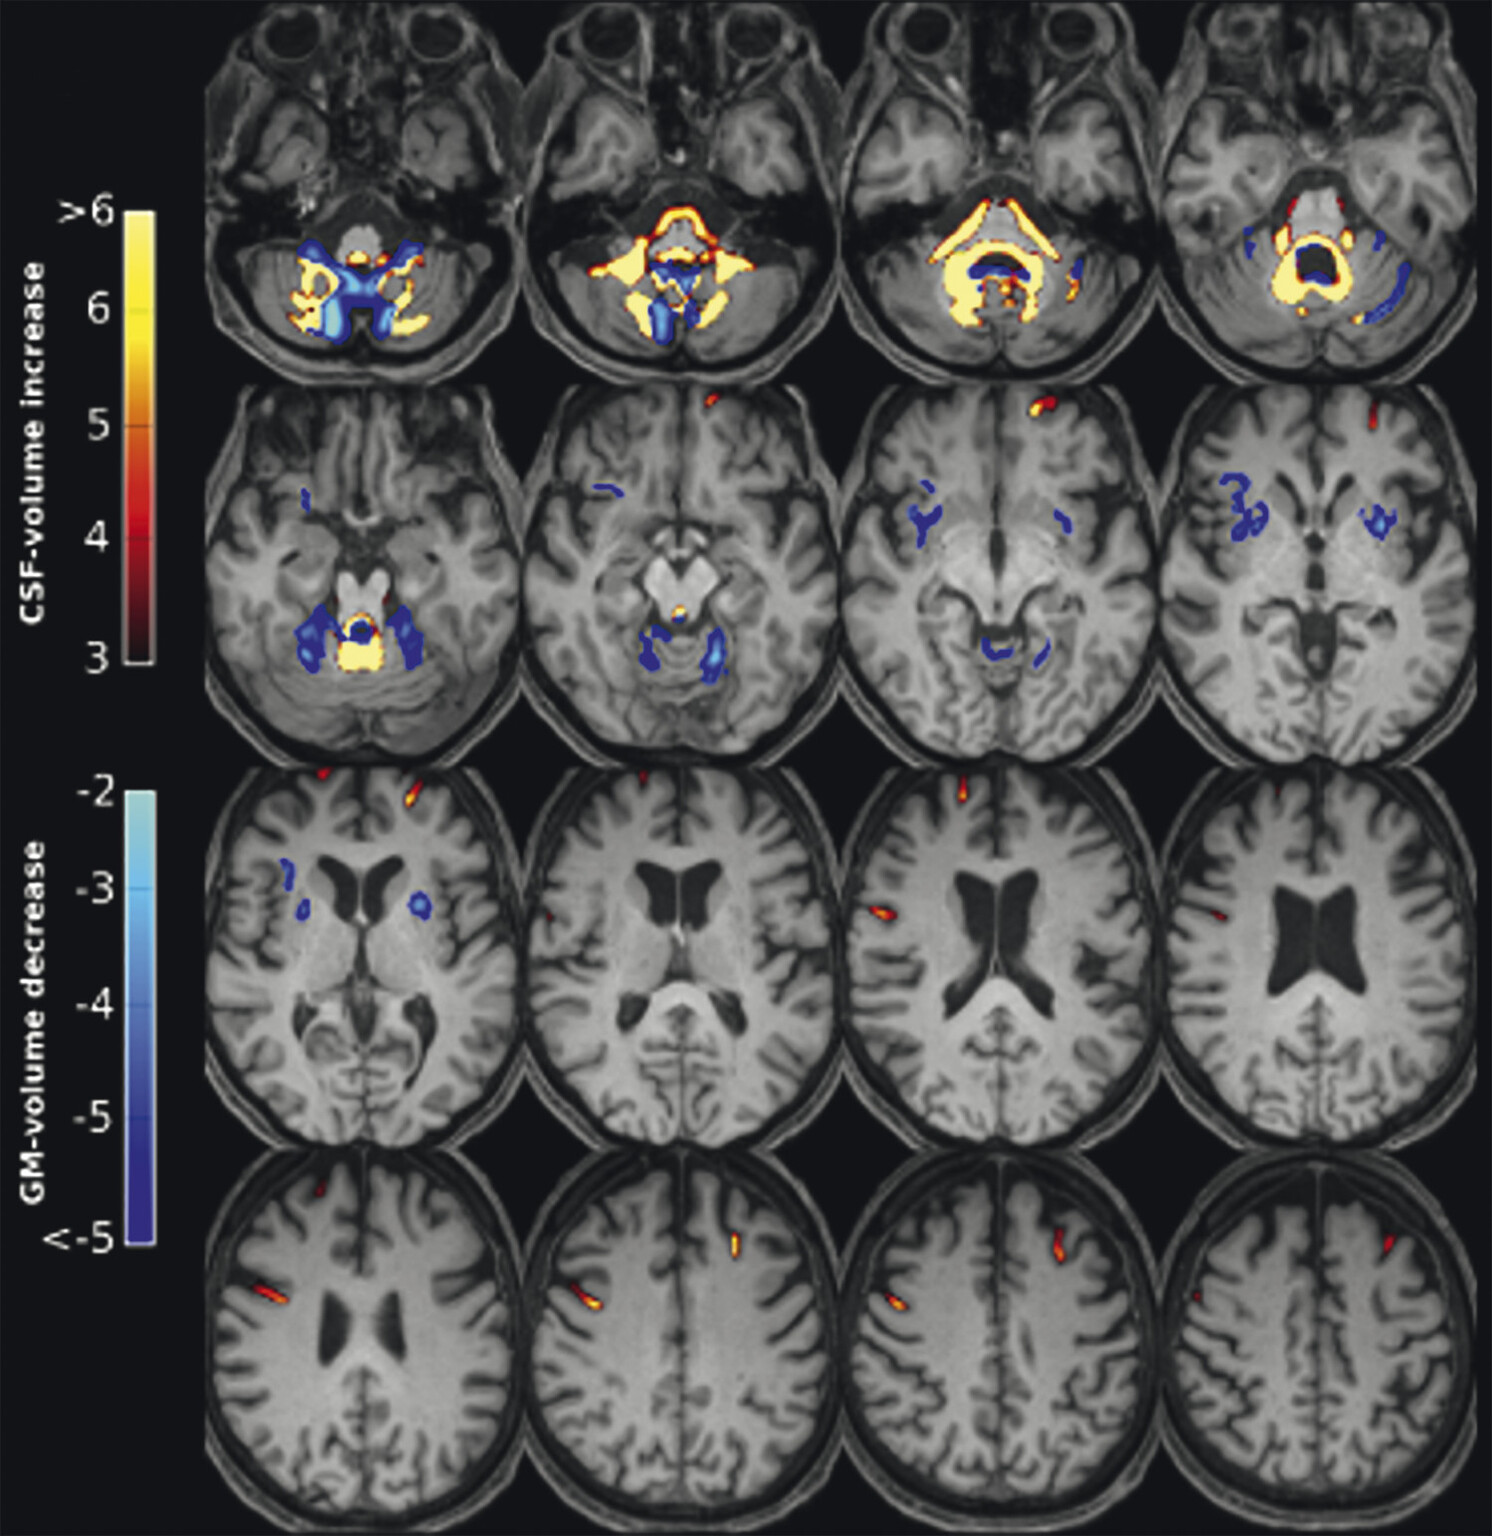

Abb. 69.7 Parkinson-Syndrome: Differenzialdiagnose Multisystematrophie vom zerebellären Prädominanztyp.

67-jährige Patientin mit über Jahre progredienter Verschlechterung des Gleichgewichts, Schluckstörungen und Sprechstörungen. In der T1w 3-D-Sequenz zeigt sich eine ausgeprägte Atrophie des Pons (a, Pfeil), der mittleren Kleinhirnstiele (b, Pfeile) und des Kleinhirns. Diese Veränderungen werden durch die Ganzhirnvolumetrie bestätigt (c): Anomale Regionen der grauen Substanz (mindestens 2 Standardabweichungen unter dem vergleichbaren Volumen des gesunden alters- und geschlechtsgematchten Normkollektivs) sind blau überlagert. Anomale Liquorvolumina (mindestens 2 Standardabweichungen über dem vergleichbaren Volumen des gesunden alters- und geschlechtsgematchten Normkollektivs) sind als rote bis gelbe Überlagerungen auf das individuelle Patientengehirn projiziert. MRT-morphologisch lässt sich somit die Verdachtsdiagnose Multisystematrophie vom zerebellären Prädominanztyp bestätigen.

a Sagittale T1w 3-D-MRT-Sequenz.

b Axiale T1w 3-D-MRT-Sequenz.

c Voxel- und regionenbasierte Analyse.